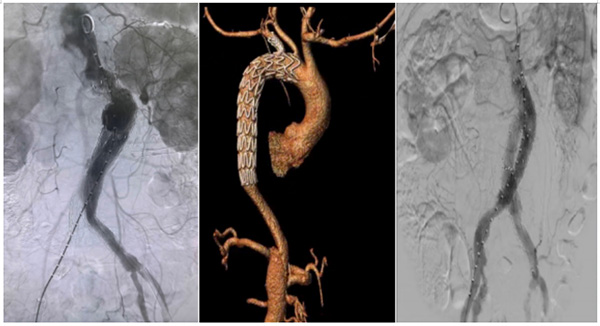

血管外科与急诊科、ICU等密切合作,为AAS患者开放绿色通道,做到24小时响应,使得该类患者能够在最短时间内完成相关检查和手术准备,及时手术,挽救生命。科室TEVAR及EVAR手术量快速增长。在国内较早利用分支型胸主动脉覆膜支架系统(WeFlow-Tbranch)及主动调控腹主动脉覆膜支架(EXCC)系统成功对复杂病例进行精准介入治疗,标志着我科在主动脉夹层救治领域跻身国内一流水平。